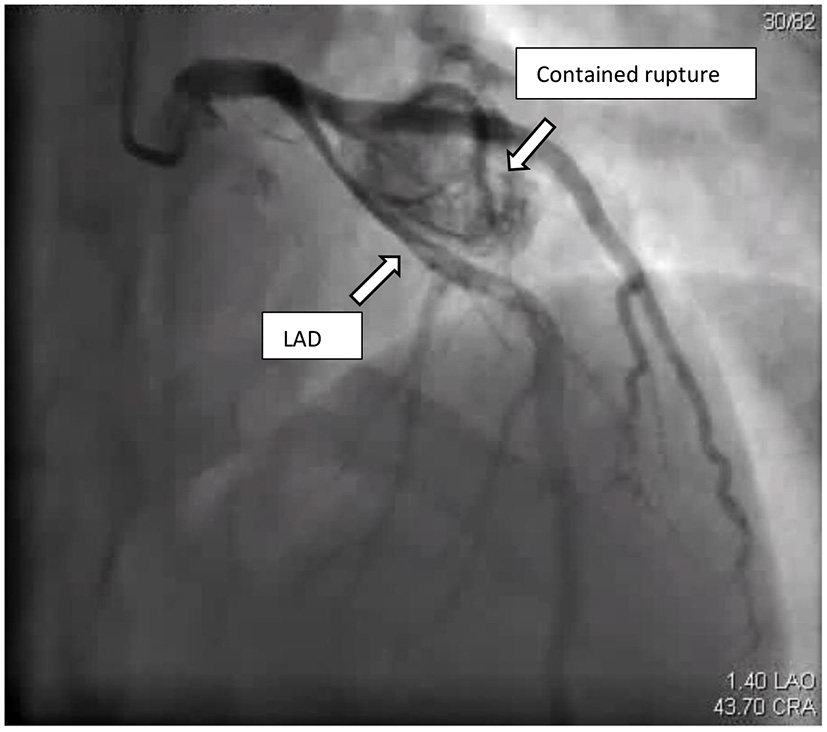

Figure 3

Coronary angiogram: cranial view, showed LAD with large contained rupture in proximal segment causing pressure effect on the LAD.

The patient was admitted to our coronary care unit as a case of ACS and was started on an ACS management protocol that includes aspirin, clopidogrel, statin, and subcutaneous heparin (enoxaparin 1 mg/kg twice daily). A transthoracic echocardiogram revealed a low normal ejection fraction (EF 50%) with mild anterior wall hypokinesia and no pericardial effusion; otherwise, no abnormality was detected (Figure 2). The patient was stabilized overnight and taken to the coronary catheterization laboratory for a coronary angiogram. The coronary angiogram showed normal left main (LM) artery, and the left anterior descending artery (LAD) exhibited a large pseudoaneurysm in proximal segment with contrast squirted in it and TIMI II-III flow in the distal LAD (Figure 3). The left circumflex artery (LCX) and the right coronary artery (RCA) were observed to be normal. The procedure was stopped, and the patient was urgently referred for a cardiac surgery consultation. Three hours later, he developed acute hypotension with a BP of 75/55 mmHg and HR of 133 bpm. Bolus IV fluid was given, and emergency bedside pericardiocentesis was performed in addition to the removal of 50 cc of fresh blood. The patient's BP stabilized, and he was taken as a lifesaving case to the operating room. Cardiopulmonary bypass (CPB) was established through the cannulation of the femoral vessels. A median sternotomy was performed, and 100 cc of fresh and clotted blood was removed from the pericardial sac. Then, careful examination of the pseudoaneurysm showed spontaneous rupture with contained bleeding. The opening of spontaneous rupture in the LAD was identified as shown in Figure 4, and it was closed with a 3–0 polypropylene continuous suture. Postoperatively, the patient did well. He did not show any signs of either myocardial infarction or left ventricle pump failure. Thus, he was discharged 6 days later in a stable condition.